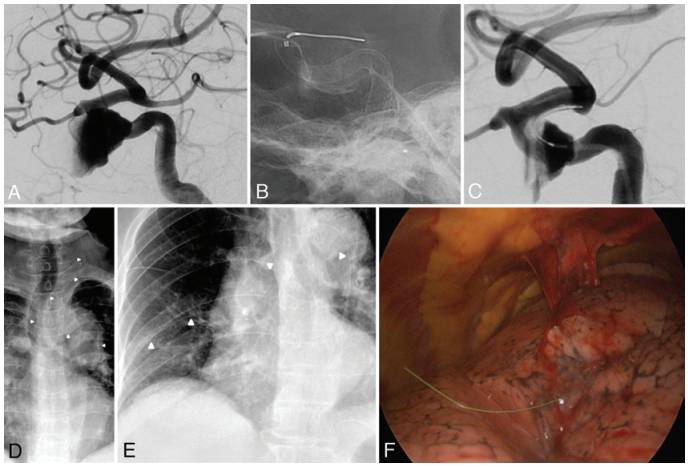

病例1,69岁女性患者,诊断为左侧未破裂颈内动脉(ICA)海绵窦段动脉瘤。3D-DSA显示,动脉瘤最大径22mm,瘤颈8mm,载瘤动脉血流流入动脉瘤端的直径3.9mm,血流流出端的直径3.8mm。术前常规阿司匹林和氯吡格雷口服5天。在全麻和全身肝素化下,将4.5×20mm的血流导向装置(Pipeline Embolization Device,PED)置入载瘤动脉并覆盖动脉瘤瘤颈,覆盖范围从ICA眼内段延伸至ICA海绵窦段后膝部,置入过程顺利(图1A)。在完全释放PED装置后发现输送PED的微导管被推至微导丝的头端后方,并已出PED腔和卡在PED与血管壁之间,采取多种措施均无法将其回撤(图1B、C)。术后1个月作胸部和头颅放射学检查,结果与术后X线检查比较,未见明显改变(图1D)。术后6周患者因全身不适、间断胸痛和股动脉穿刺部位渗血返院;复查头颅X线片,未见PED或遗留的导丝头端有异常变化;但是胸部X线片提示,右侧肋膈角钝化,从右侧气管旁区至右下胸侧壁出现菲薄曲线结构改变(图1E)。胸部CT显示,一段金属丝自右上肺叶的内侧面穿透右肺到右下肺叶的外侧面。胸腔镜图像中,可见一段导丝刺穿右肺的脏层胸膜,导致局部出血和胸膜粘附(图1F)。最后,顺利取出近55cm长的导丝(图3A),无并发明显的胸膜缺损。

图1. 病例1的DSA、X线和胸腔镜检查结果